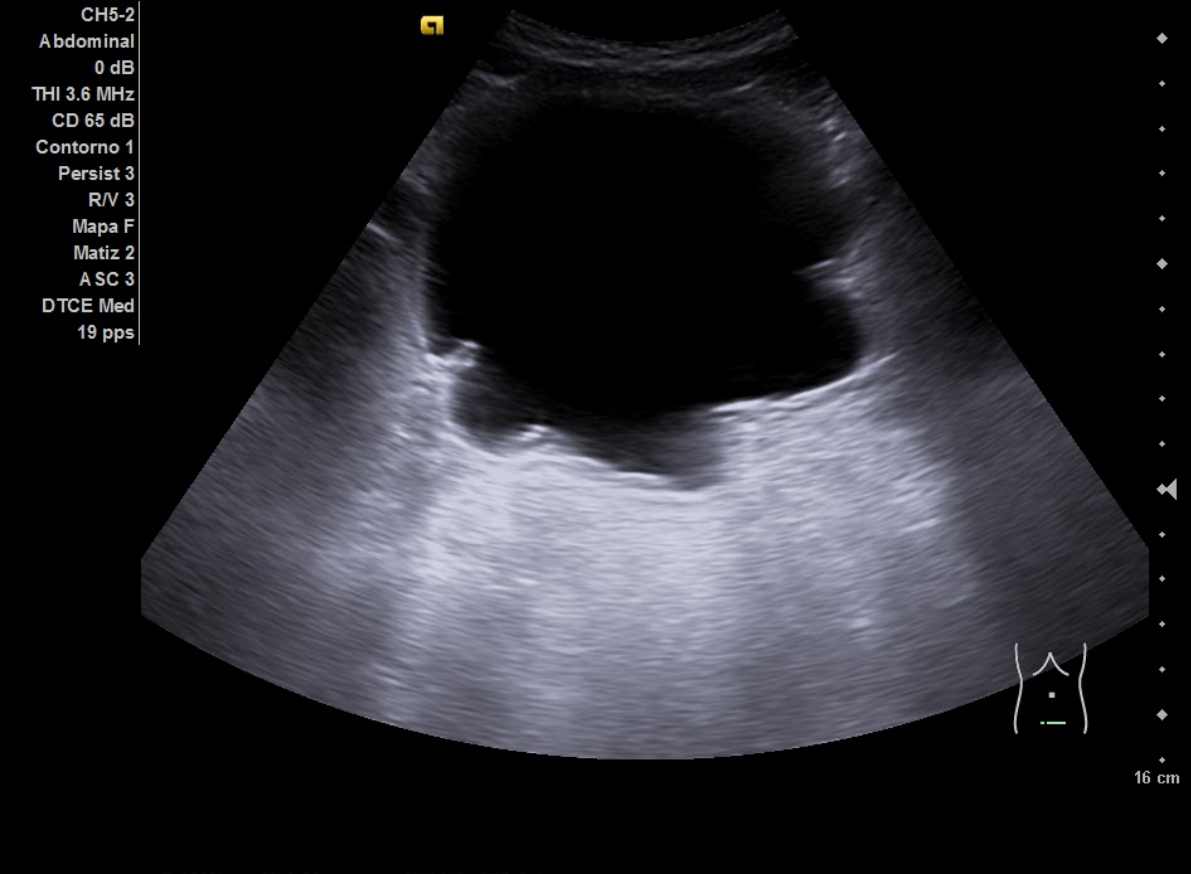

Hallazgos ecográficos

Ecografía aparato urinario en Centro de Salud: Riñones de tamaño normal, parénquima conservado con dilatación pielocalicial grado II-III izquierdo y grado II derecho. Vejiga con aspecto trabeculado, pared irregular con divertículos. Volumen premiccional 550 cc, postmiccional 450 cc. Volumen prostático de 50 cc.